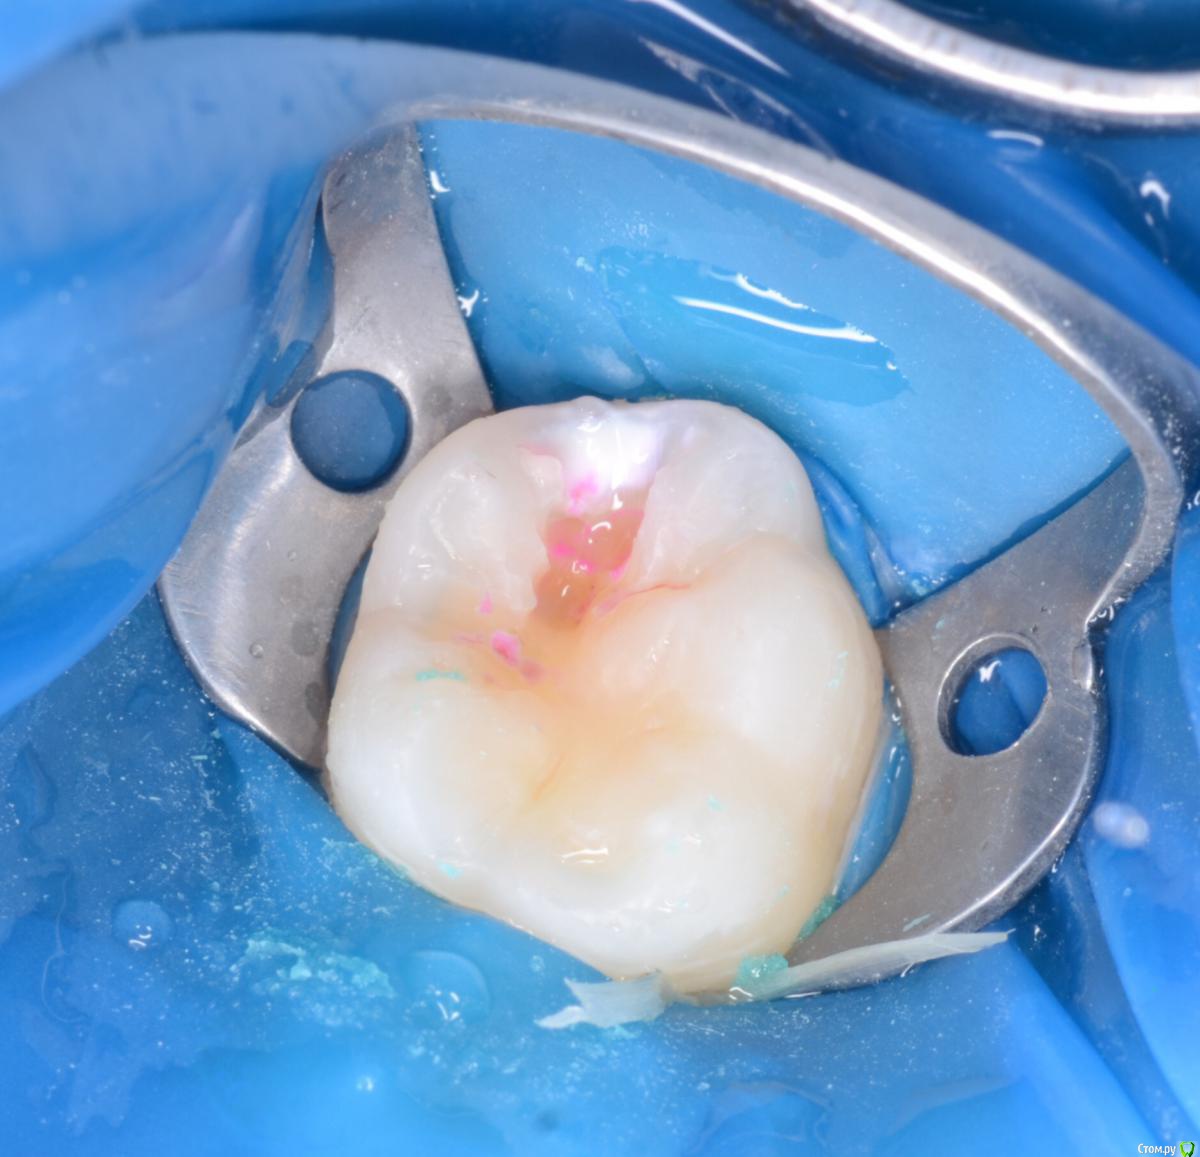

CRAZYDUCK Опубликовано 24 мая, 2018 Автор Поделиться Опубликовано 24 мая, 2018 В этом клиническом случае хочу обратить внимание коллег на покрытие 8.5 зуба коронкой ( что необычного видите ?). И на использование флосса, чтобы заправить платок дистально за 4.6 . 4.6 начальный кариес , но зуб дистально ещё был прикрыт десной ( фото до лечения не делала без коффердама). Раньше во время работы в эту дистальную зону «трамбовала» Фумку . Следила , чтобы не подтекало . Но !!!!Очень удобно эту десну заправлять флоссом - ничего не течёт 1 Ссылка на комментарий

CRAZYDUCK Опубликовано 24 мая, 2018 Автор Поделиться Опубликовано 24 мая, 2018 8.5 ранее лечен методом витальной ампутации( 1,5 года назад ), но реставрация обширная . Не выдерживает жевательную нагрузку . 2 Ссылка на комментарий

CRAZYDUCK Опубликовано 24 мая, 2018 Автор Поделиться Опубликовано 24 мая, 2018 Я всегда перед лечением очищаю зубы кавопрофифлекс ( все зубы , которые попали в зону изоляции ), поэтому изначально планировали только покрыть 8.5 коронкой . Из-за этого изоляция такая ( никакая), но после чистки 4.6 стало ясно , что планы немного меняются . Ссылка на комментарий